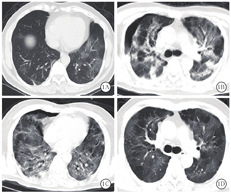

新冠肺炎患者胸部CT表现为:①早期:病变局限,呈斑片状、节段性磨玻璃影,多伴有小叶间隔增厚;②进展期:病灶增多、范围扩大,可累及多个肺叶,部分病灶实变,磨玻璃影与实变影或条索影共存;③重症期:双肺呈弥漫性病变,以实变影为主,合并磨玻璃影,多伴条索影,支气管充气征[1]。本组患者胸部CT显示病灶进展均较快,1例在1周内从早期演变为进展期,2周内演变为重症期,4周后并发气胸,2周后气胸吸收(图1);其余6例患者入院时胸部CT即表现为进展期,均在1~2周内进展为重症期,多表现为双肺弥漫性实变影、条索影及纤维化,胸膜粘连明显,病灶吸收极缓慢(图2)。由于患者病情进展快,病情危重时难以行胸部CT检查,导致影像学资料不齐全。